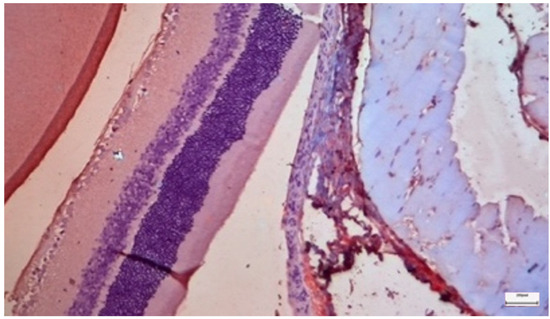

Background/Objectives: Cisplatin is a potent chemotherapeutic agent whose clinical utility is limited by severe side effects, including neurotoxicity affecting the ocular system. The pathophysiology involves oxidative stress and mitochondrial dysfunction, to which the retina is particularly vulnerable. Selenium (Se), an essential trace element and component of antioxidant enzymes, has shown potential in mitigating cisplatin toxicity, although its efficacy with respect to retinal structure and the influence of administration routes remain underexplored. This study aimed to evaluate the protective efficacy of selenium against cisplatin-induced retinal toxicity and compare the effects of intraperitoneal and oral selenium administration. Methods: Forty adult male Wistar rats were randomized into four groups (n = 10 each): Group A (Cisplatin Monotherapy, 3.5 mg/kg IP for 5 days; cumulative dose 17.5 mg/kg); Group B (Cisplatin + Intraperitoneal Selenium, 2.73 mg/kg; cumulative dose 60 mg/kg); Group C (Control); and Group D (Cisplatin + Oral Selenium). Selenium prophylaxis, administered as sodium selenite (Na2SeO3), began two days prior to cisplatin administration and continued for 15 days post-treatment. Retinal evaluation two weeks after cisplatin cessation included light microscopy, semi-quantitative immunohistochemical (IHC) analysis for inflammatory (IL-6) and fibrotic (TGF-β2) markers, and Transmission Electron Microscopy (TEM) for ultrastructural analysis, which were the primary endpoints. Statistical differences in the IHC scores were analyzed via the Kruskal‒Wallis H test with Dunn’s post hoc comparisons. Results: Cisplatin monotherapy (Group A) caused severe disruption of the retinal architecture, including edema, reactive gliosis, and significant upregulation of IL-6 and TGF-β2. Ultrastructural analysis revealed mitochondrial swelling (cristolysis) and photoreceptor disk fragmentation. Intraperitoneal selenium (Group B) was associated with significant structural preservation and intact mitochondria, with TGF-β2 levels comparable to those of the controls, although the IL-6 level remained moderately elevated. Conversely, oral selenium (Group D) suppressed both IL-6 and TGF-β2 expression to near-negative levels but provided less ultrastructural protection, resulting in persistent mitochondrial swelling and focal photoreceptor disruption. Conclusions: Systemic cisplatin induces severe subcellular retinal toxicity characterized by mitochondrial damage and photoreceptor degeneration. Selenium supplementation attenuates these effects; however, outcome patterns differ by administration route. Intraperitoneal selenium was associated with greater morphological and ultrastructural preservation despite persistent IL-6 elevation, whereas oral selenium normalized immunohistochemical marker expression to near-control levels but was associated with more pronounced residual subcellular damage on qualitative TEM assessment. These preliminary morphological and immunohistochemical findings suggest that the route of selenium delivery may influence its neuroprotective profile; however, pharmacokinetic measurements and functional retinal assessments, such as electroretinography, are warranted before its clinical translation. Full article